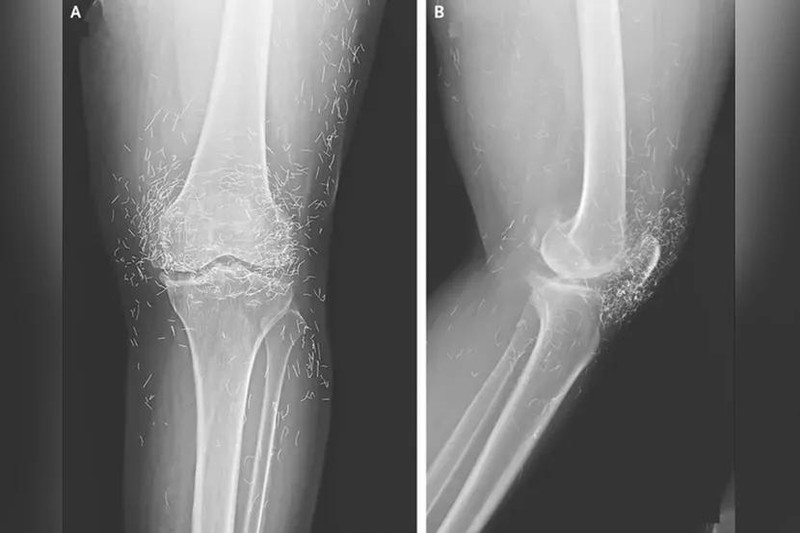

Kết quả chụp X-quang cho thấy tình trạng dày và cứng bất thường ở phần xương chày trong, sự phát triển của gai xương quanh đầu gối – những triệu chứng điển hình của thoái hóa khớp – cùng với hàng trăm sợi chỉ vàng li ti được cấy vào các mô quanh khớp.